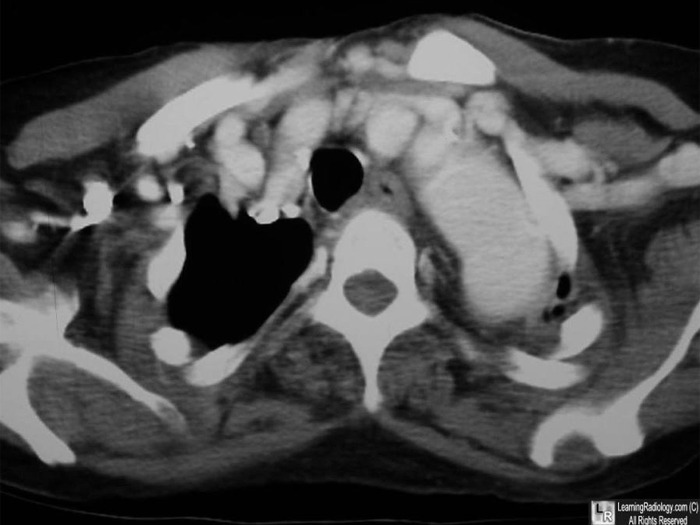

Cervical Aortic Arch. Above: Axial, contrast-enhanced CT scan of the upper thorax shows the aortic arch (black arrow) extending above the level of the clavicles. Below: Frontal radiograph of the chest demonstrates the cervical arch at the apex of the left lung (white arrow) above the clavicles. There is no aortic arch in the normal location. The aorta descends on the left.

For this same photo without the arrows, click here and here